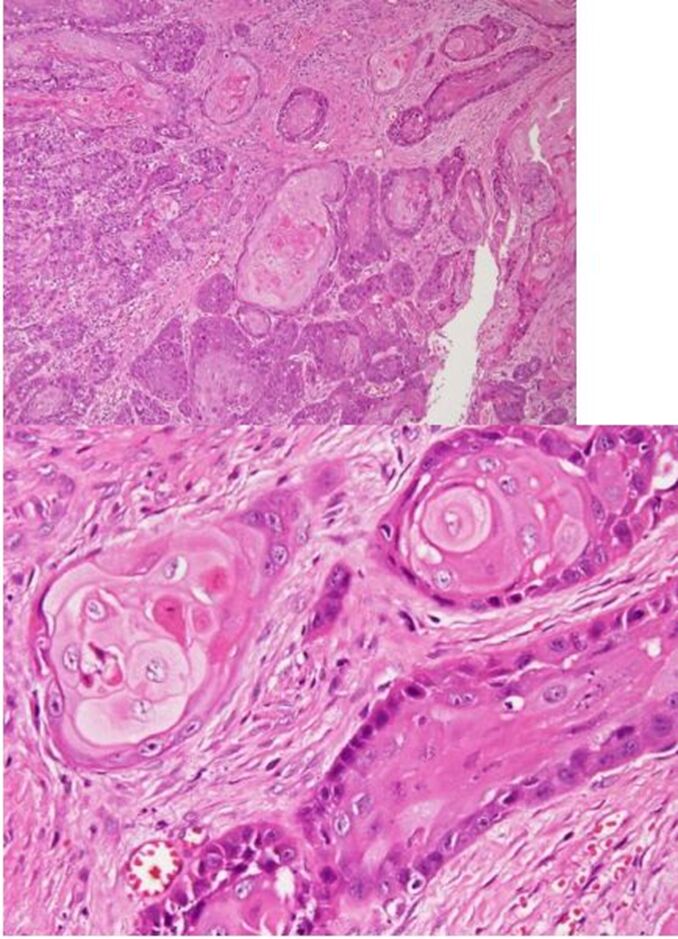

62.下圖為犬趾端潰瘍與骨溶解病灶區的肉眼與組織病變,最適當的診斷為:

(B)infundibular keratinizing acanthoma

(C)squamous cell carcinoma

62.下圖為犬趾端潰瘍與骨溶解病灶區的肉眼與組織病變,最適當的診斷為: |